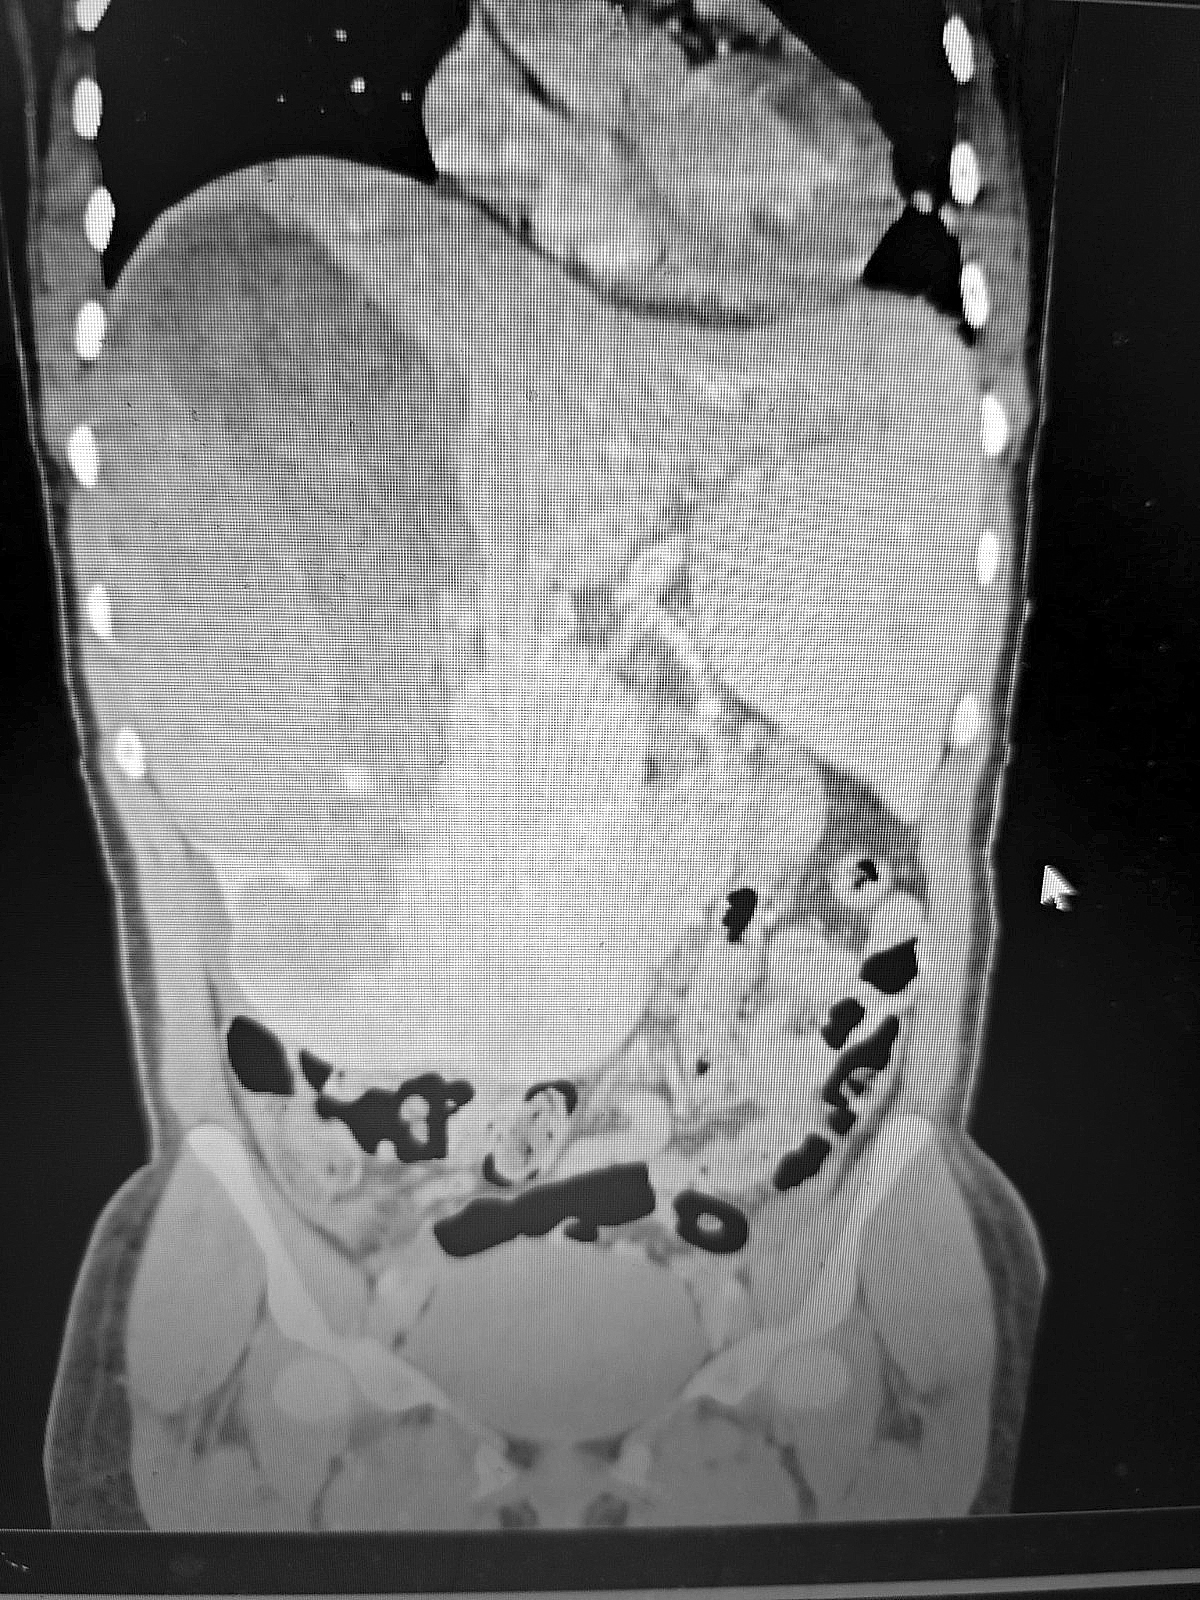

El Dr. Emilio Tonina, cirujano general del Hospital IPS Ingavi, explicó que los estudios de imágenes revelaron la presencia de una tumoración de gran tamaño en el lóbulo derecho del hígado. A pesar del soporte transfusional, la paciente continuó presentando inestabilidad, por lo que se indicó una cirugía de urgencia.

Durante la intervención se logró extraer un tumor de 12 centímetros de diámetro y 1,8 kilogramos de peso, mientras que el lóbulo derecho del hígado medía aproximadamente 15 centímetros. El resultado de la biopsia confirmó que se trataba de un hemangioma cavernoso gigante, mayor a 12 cm, complicado con una hemorragia intraparenquimatosa. Este tipo de tumor benigno de origen vascular es el más frecuente del hígado y se presenta con mayor incidencia en mujeres.